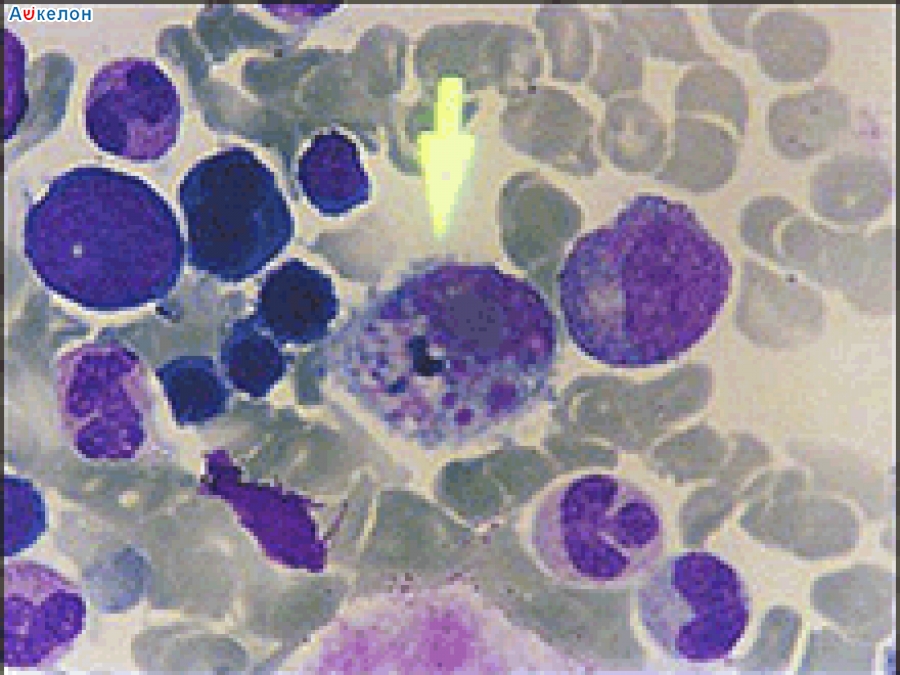

'На днях он скончался в лондонской больнице от крымско-конголезской вирусной геморрагической лихорадки. Симптомы этой болезни — головная боль, а также боли в суставах, тошнота и высокая температура.